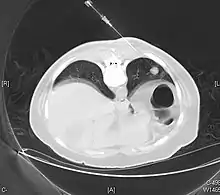

.jpg.webp)

The definitive diagnosis is rendered by a microscopic examination, after excision. Typical carcinoids have cells with stippled chromatin and a moderate quantity of cytoplasm. They typically have few mitoses and lack necrosis. By definition, they are greater than 4 mm in largest dimension; smaller lesions are referred to as pulmonary carcinoid tumourlets.